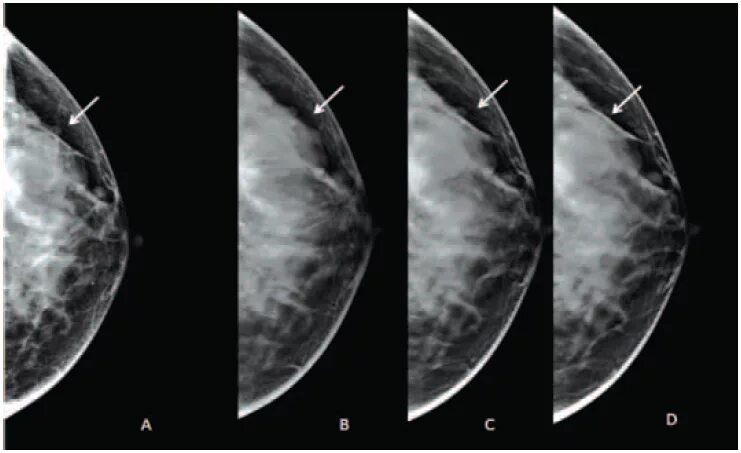

Что значит кальцинат в молочной железе